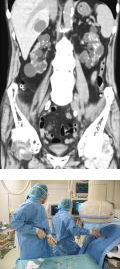

透析関連画像診断